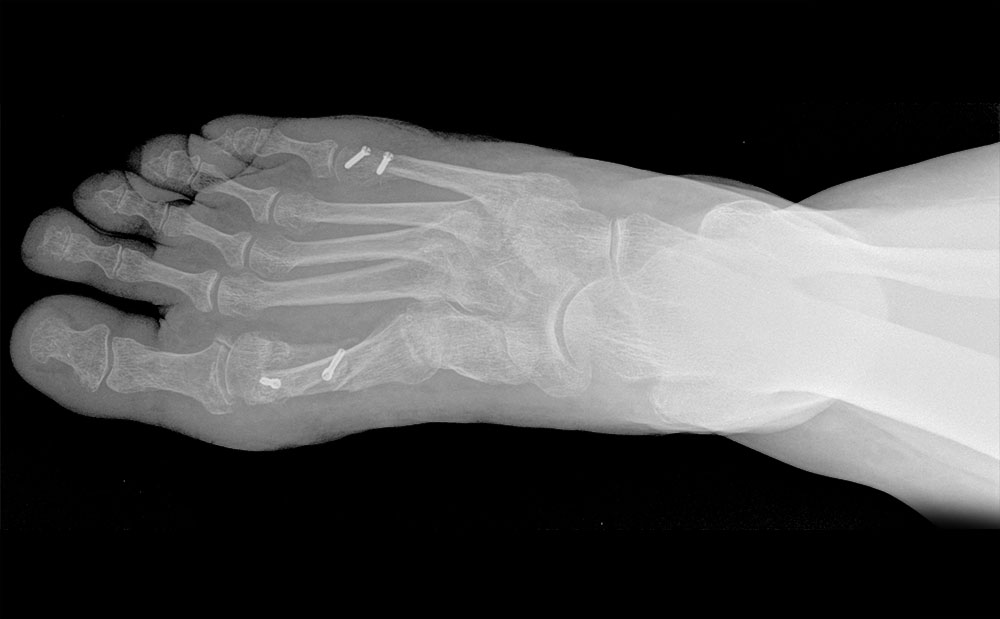

Forma leczenia operacyjnego dobierana jest w zależności od typu deformacji. Stosowane jest ścięcie bocznego fragmentu głowy V kości śródstopia lub osteotomia (przecięcie) V kości śródstopia. Przecięcie można wykonać w okolicy podgłowowej (typy Chevron, Weil) lub w obrębie trzonu. Po przecięciu kości wykonuje się przesunięcie głowy 5 kości śródstopia w kierunku przyśrodkowym oraz zespolenie za pomocą implantu. Należy również wykonać plastykę tkanek miękkich w obrębie stawu śródstopno-palcowego palca V.

Dodatkowo, w niektórych przypadkach możliwe jest leczenie miniinwazyjne deformacji bunionette. Za pomocą niewielkich cięć skórnych dokonuje się przecięcia V kości śródstopia oraz usuwa się nadmiar bocznej części głowy tej kości.